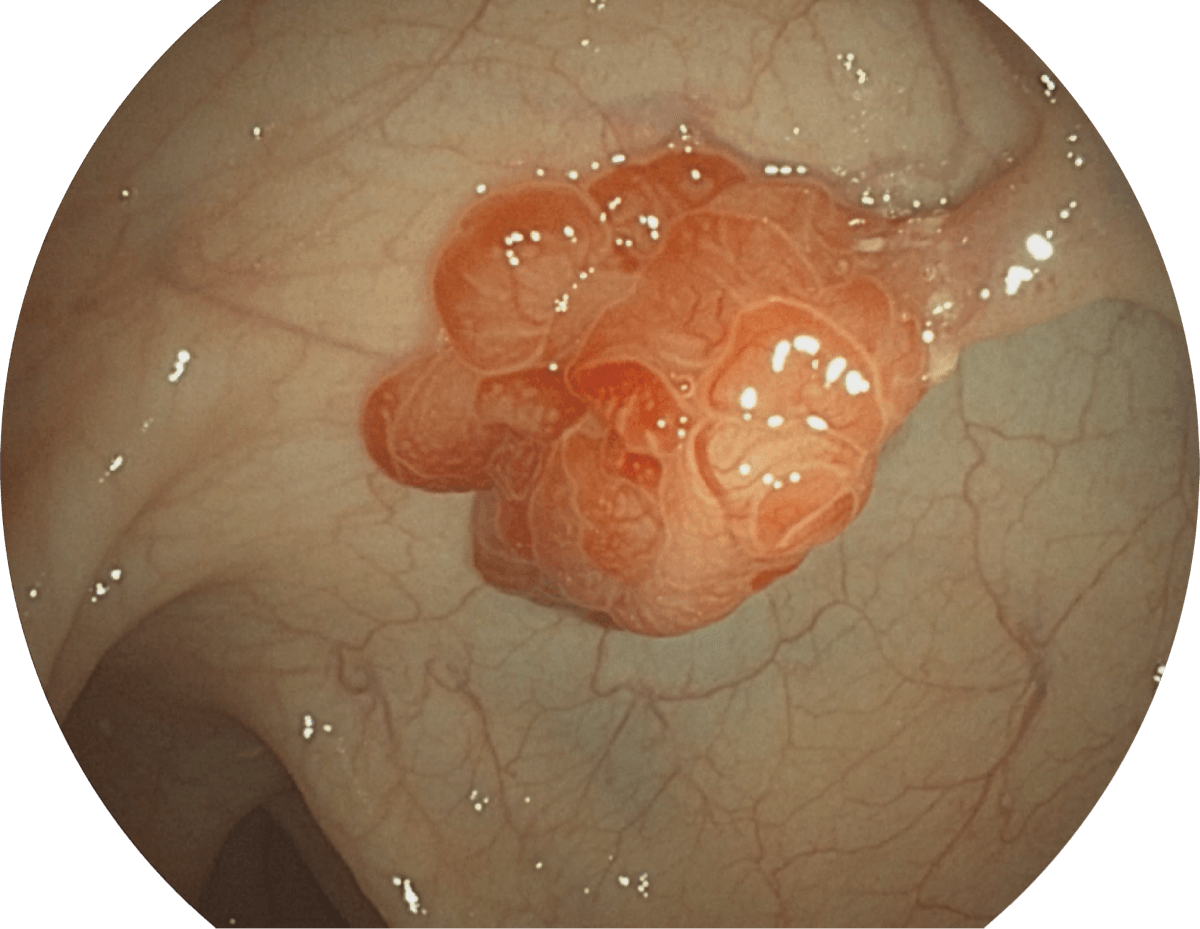

具有聚谱成像技术(SFI)及光电复合染色成像技术(VIST),可完美呈现粘膜细节及病变特征。

(Spectral Focused lmaging, SFI)

WL